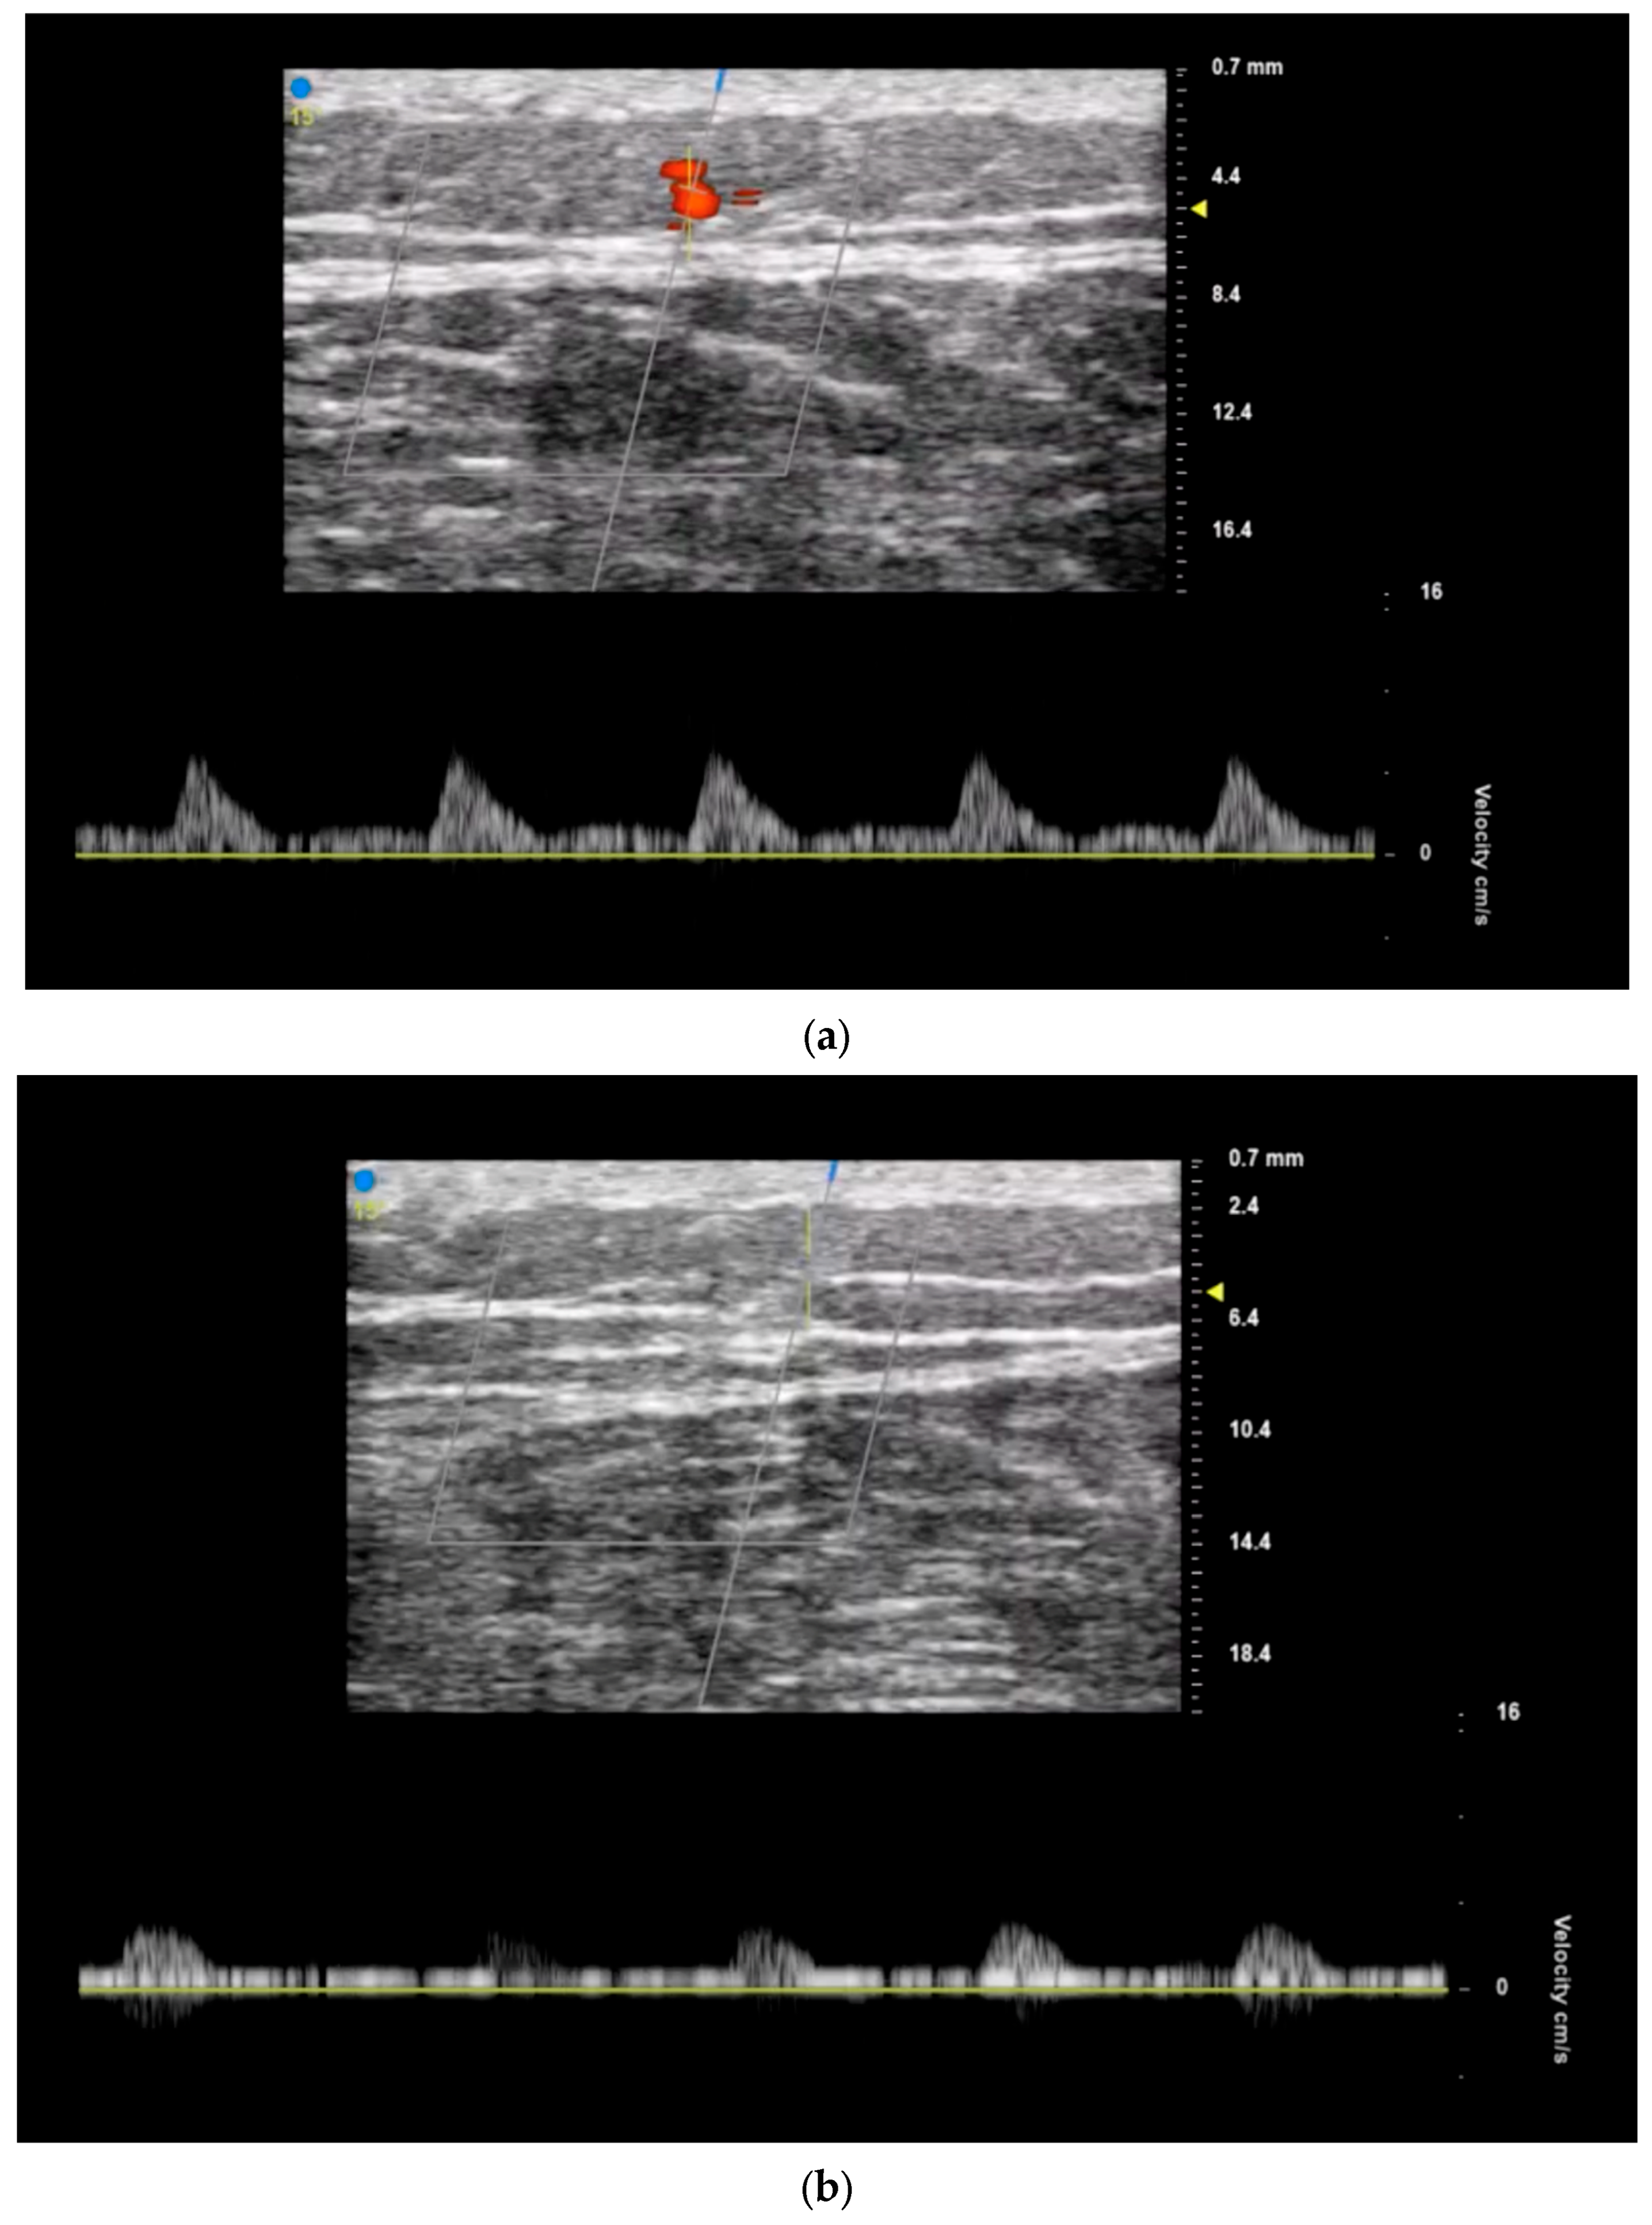

3.2. Recipient Vessel Selection

- Hong, J.P.; Kim, H.B.; Park, C.J.; Suh, H.P. Using Duplex Ultrasound for Recipient Vessel Selection. J. Reconstr. Microsurg. 2022, 38, 200–205. [Google Scholar] [CrossRef]